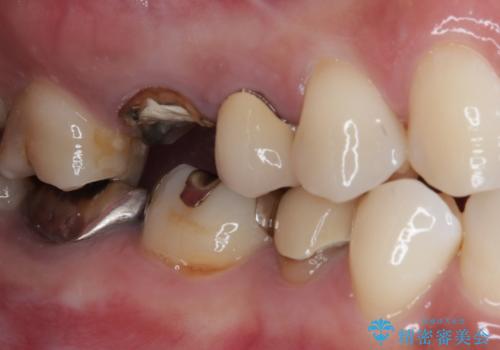

- 近医にて治療がなかなか進まないとのことで来院された患者様です。

詰めている材料を外したところ、目視で確認できるほど割れており、要抜歯との説明をし、インプラント治療を行うこととしました。

骨量が十分にあることが3次元CTより確認されたため、事前に仮歯を用意した上で、抜歯即時埋入インプラントによる補綴治療を行うこととしました。